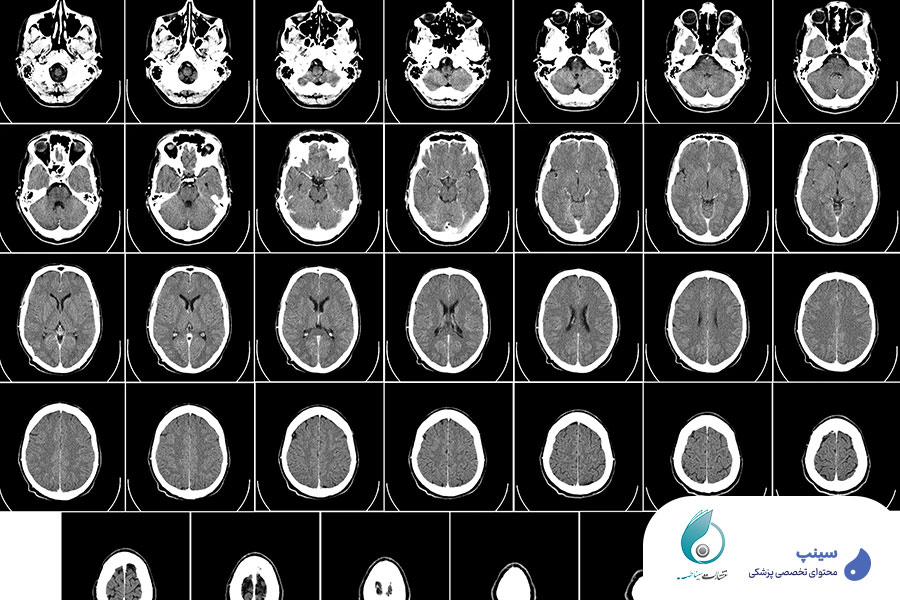

رادیولوژی امروزه به عنوان یکی از شاخه های حیاتی پزشکی، نقش مهمی در تشخیص و مدیریت بیماری های مختلف دارد. امروزه با پیشرفت چشمگیر فناوری های تصویربرداری پزشکی، مثل سیتیاسکن و MRI، پزشکان میتوانند با کمک تصاویر بدست آمده که از نمونه های چند سال پیش بدون شک بهتر و باکیفیت تر هستند، اطلاعات دقیقی از شرایط بیمار کسب نمایند. این ابزارها به خصوص برای تشخیص و ارزیابی شرایط پیچیده ای مثل بیماری های مغزی بسیار کارآمد و موثر خواهند بود. اما صرفا داشتن این تصاویر کافی نیست، بلکه باید تفسیر و تحلیل این تصاویر به همراه یک ریپورت نویسی جامع و دقیق وجود داشته باشد تا بتوان در مورد تشخیص بیماری ها تصمیم گرفت.

مغز دارای ساختار بسیار پیچیده و حساسی است و از این رو تشخیص بیماری های مربوط به این ناحیه از بدن، نیازمند دقت و تامل بسیار بالا است. بسیاری از بیماری های مغزی، از جمله آسیب های عروقی، تومورها، اختلالات عصبی و غیره تنها از طریق تصاویر دقیق و باکیفیت سی تی اسکن یا ام ار آی مغز قابل تشخیص خواهند بود. مهارت در ریپورت نویسی، میتواند تفاوت بزرگی در تشخیص درست و به موقع این بیماری ها ایجاد نماید. بدون شک، تشخیص به موقع، میتواند در درمان بیمار بسیار کاربردی باشد.

این بخش، شامل آموزش های ضروری درباره ساختارهای مختلف مغز و چگونگی تحلیل و تشخیص آنها در تصاویر ام آری آی و سی تی اسکن مغزی خواهد بود.

دکتر نصیری، در بخش های میانی آموزش، شما را با انواع ضایعات و ناهنجاری های شایع در مغز آشنا خواهد کرد تا بتوانید در تصاویر با دقت و سرعت بیشتری آنها را تشخیص دهید. همچنین نحوه تفسیر و گزارش آنها را به صورت کامل یاد خواهید گرفت. توجه داشته باشید این قسمت آموزش، بر اساس کیس های واقعی طراحی شده است.

یکی دیگر از بخش های مهم دوره ریپورت نویسی سی تی و MRI مغز، مربوط به تفسیر و ریپورت نویسی در مورد تومورهای مغزی و ضایعات عروق مغز است. این بخش به شما یاد میدهد که چگونه ضایعات مختلف را از یکدیگر تمییز داده و در مورد هر کدام، اطلاعات کافی و دقیق به پزشک معالج ارائه نمایید.

در اینجا شما یاد میگیرید که چگونه با تجزیه و تحلیل تصاویر سی تی اسکن و ام آر آی مغز، بیماریهای شایع عصبی را شناسایی کنید و در مورد آنها گزارش بنویسید. بیماری های شایع عصبی مانند سکته مغزی، ام اس و دیگر اختلالات عصبی در این قسمت از آموزش، بررسی خواهند شد.